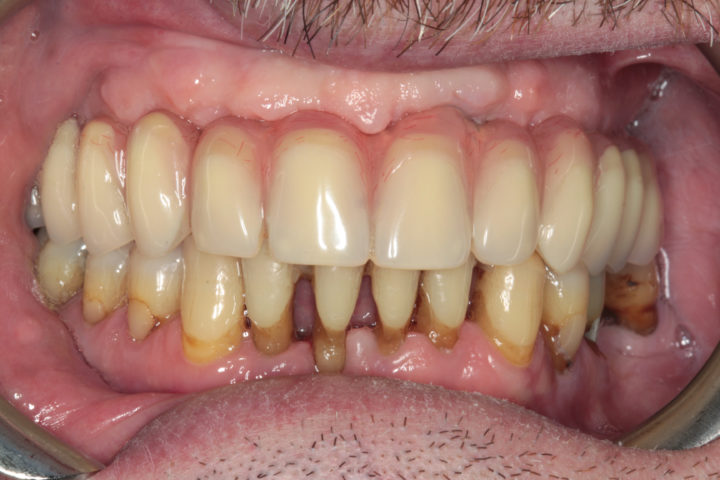

PRIMA

dopo

Arcata superiore - Fase iniziale, intermedia e finale

Caso risolto con Toronto Bridge - Fase iniziale, intermedia e finale